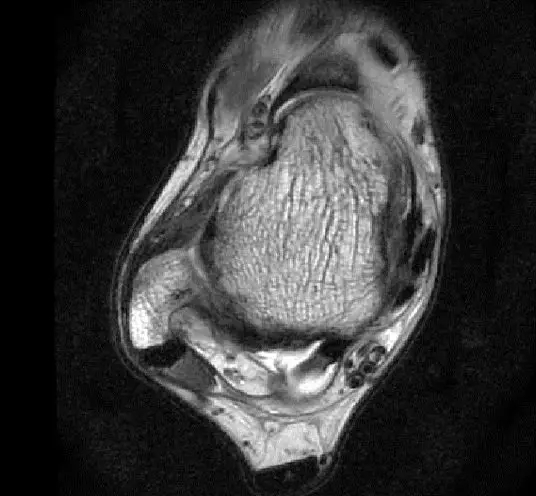

此片可以看到韧带结构消失,T2相高信号,整体韧带增粗,松弛,腓骨肌腱内侧,跟绯肌腱的形态完全消失,它的韧带也是松弛增粗的。所以考虑是踝关节距腓前韧带的损伤。